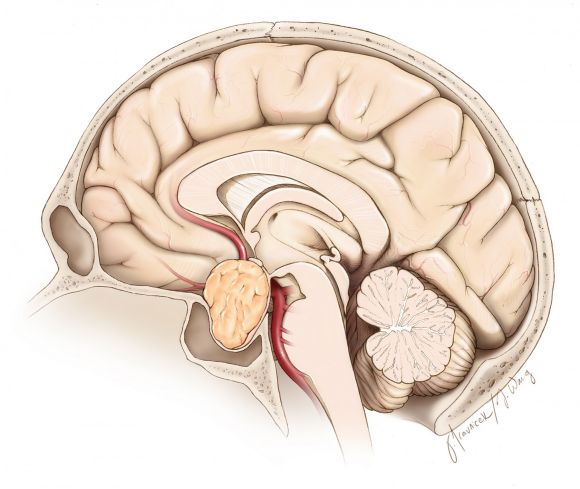

图2. 垂体大腺瘤为直径大于10mm并对周围结构有占位效应的垂体瘤。临床上最常见的压迫症状为压迫视交叉和/或视神经造成双颞侧偏盲。

图3. 图示典型垂体腺瘤矢状位形态。注意垂体受压至肿瘤上方或后方。